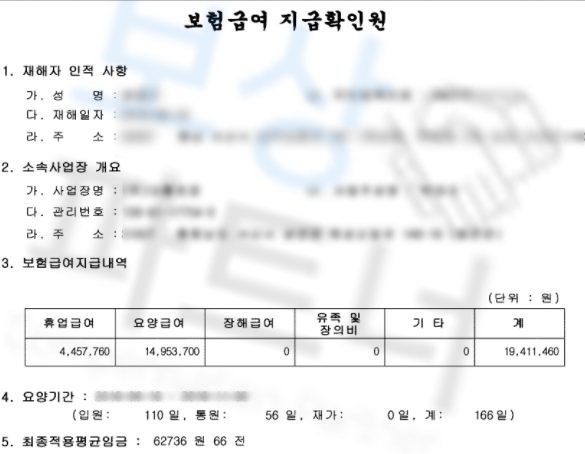

강@@님은 산재처리를 하셔서 얼마나 보상받으셨을까요? 3가지 항목에서 보상받으셨습니다.

먼저** 요양급여 14,953,700원**입니다. 요양급여는 공단이 설치 또는

보험급여를 의미합니다.

또 휴업급여 4,457,760원 보상받으셨습니다. 휴업급여는** 업무상 재해를 당하거나**

3일 이내인 경우는 지급되지 않습니다.

최초 휴업급여 신청하실 때 근로계약서 사본과 임금대장 사본을 휴업급여 청구서와 함께 신청하셔야 하고 그 이후부터는 휴업급여 청구서만 제출하면 보험급여가 지급됩니다.